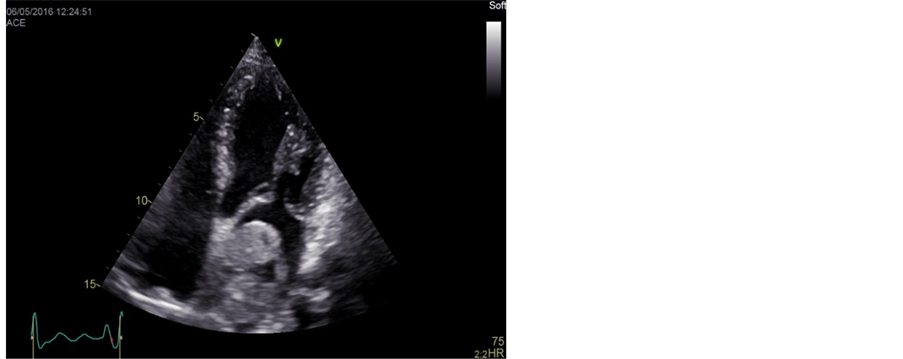

Transthoracic echocardiography revealed a tumour originating from the interatrial septum fossa ovalis in the left atrium (Figure 1). To determine the size and shape a CT-scan of the heart was conducted; the tumour measured 51 × 49 × 37 mm (Figure 2). Coronary angiography revealed abnormal arterial supply from RCA and CX to the tumour (Figure 3).

Figure 2. Computed tomography of the heart with intravenous contrast demonstrating a large filling defect in the left atrium. The myxoma measured 51 × 49 × 37 mm.